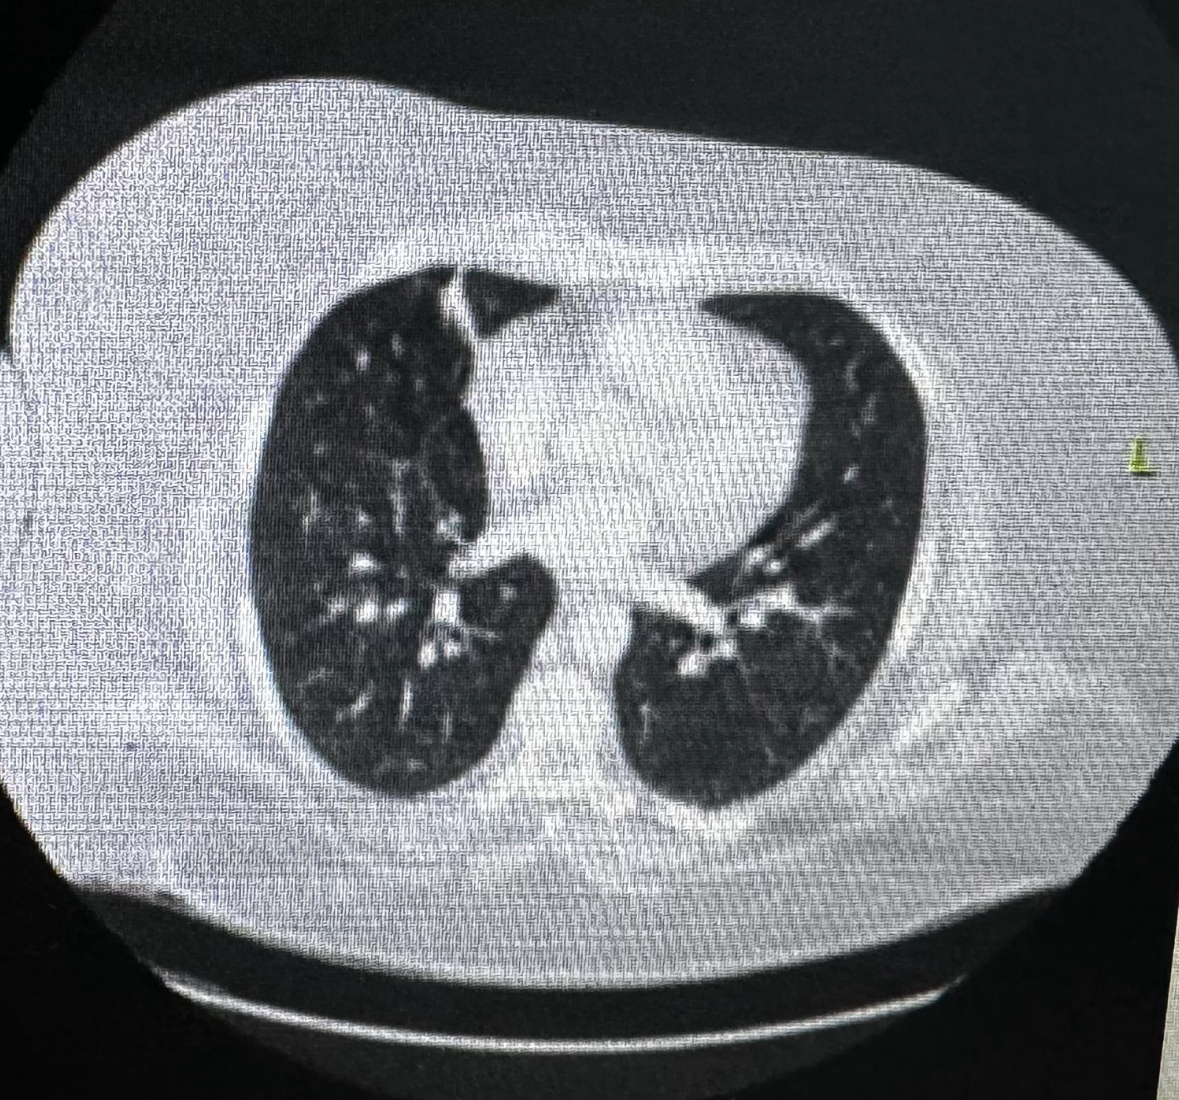

Case Presentation: A 43-year-old African-American ex-smoker with a history of biopsy-proven multisystem sarcoidosis in remission, morbid obesity, and pulmonary hypertension presented with left lower quadrant pain and was found to have multiple ventral hernias containing bowel loops without any obstruction on CT scan, following which she was discharged with outpatient surgery follow-up. Prior to contrast administration, she was pre-treated with Benadryl due to a documented contrast allergy listed as “sneezing.” Later that day, she presented with severe shortness of breath, presenting with hypoxia, tachypnea, tachycardia, with a chest X-ray showing bilateral pulmonary infiltrates, while point-of-care ultrasound showed B-lines and normal contractility of the heart. Initial labs showed elevated lactate, normal blood gases, and brain-natriuretic peptide. She was treated with IV furosemide, but she developed hypotension, prompting suspicion of contrast-induced anaphylaxis. Treatment included IM epinephrine, steroids, and bilevel-positive airway pressure (BIPAP) support, yielding some improvement, followed by an epinephrine drip and a lower dose of furosemide. Quickly, she was weaned off BIPAP and pressors in 24 hours.

Discussion: Initially, the patient was treated for congestive heart failure with diuresis. However, persistent respiratory distress, euvolemic status, hypotension, and documented mild allergic reaction (though pre-treated with Benadryl) raised suspicion for contrast-induced flash pulmonary edema. Severe contrast reactions requiring hospitalization are rare (0.004%) [1], with pulmonary edema being even rarer (0.001%-0.008%) but potentially life-threatening, underscoring the need to understand pathophysiology. This case underscores the importance of understanding the pathophysiology, hypothesized to involve vasodilation and increased permeability causing alveolar edema [2]. Notably, vasodilators like furosemide, which transiently dilates vessels, may worsen respiratory distress in already pre-dilated vessels initially, as observed in our patient.